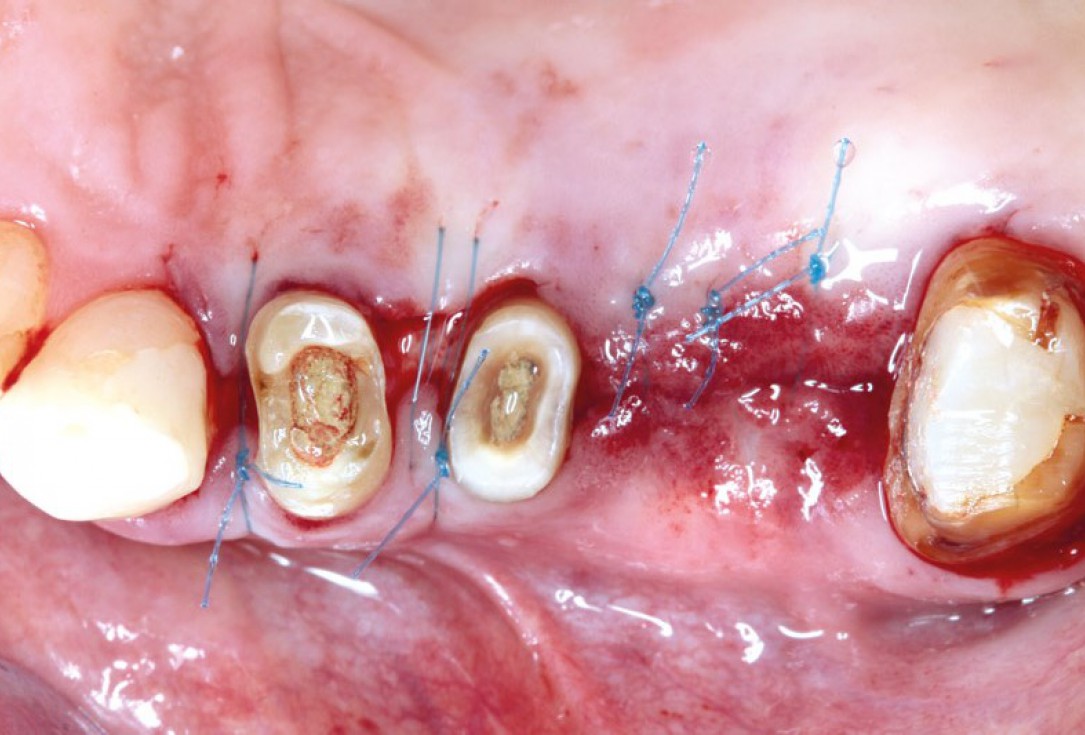

botiss cerabone® & Jason® membrane for GBR - Clinical case by Prof. Dr. Dr. D. Rothamel

Instable bridge situation with abscess formation at tooth #15 after apicoectomy